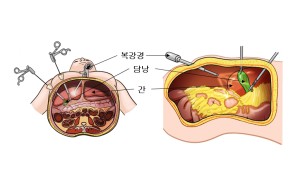

증상이 없는 경우에는 특별한 치료가 필요 없습니다. 비만인 환자의 경우 체중을 감량하고 과식을 피하며 기름진 음식을 피하는 등 생활 습관을 바꾸는 것이 도움이 됩니다. 그러나 증상이 있다면 담낭절제술을 시행할 수 있습니다.